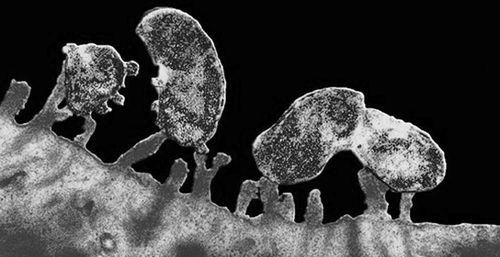

- Фиброгастродуоденоскопия з біопсією. Дозволяє оцінити стан слизової оболонки шлунка. Якщо гастрит на ранній стадії, слизова буде набряклою, набряклою, можуть спостерігатися виразки і ерозійні процеси. Якщо гастрит запущений, слизова буде блідою, атрофичной, з деформованими структурами епітелію. Біопсія нерідко дозволяє виявити фомирующейся ракові клітини.